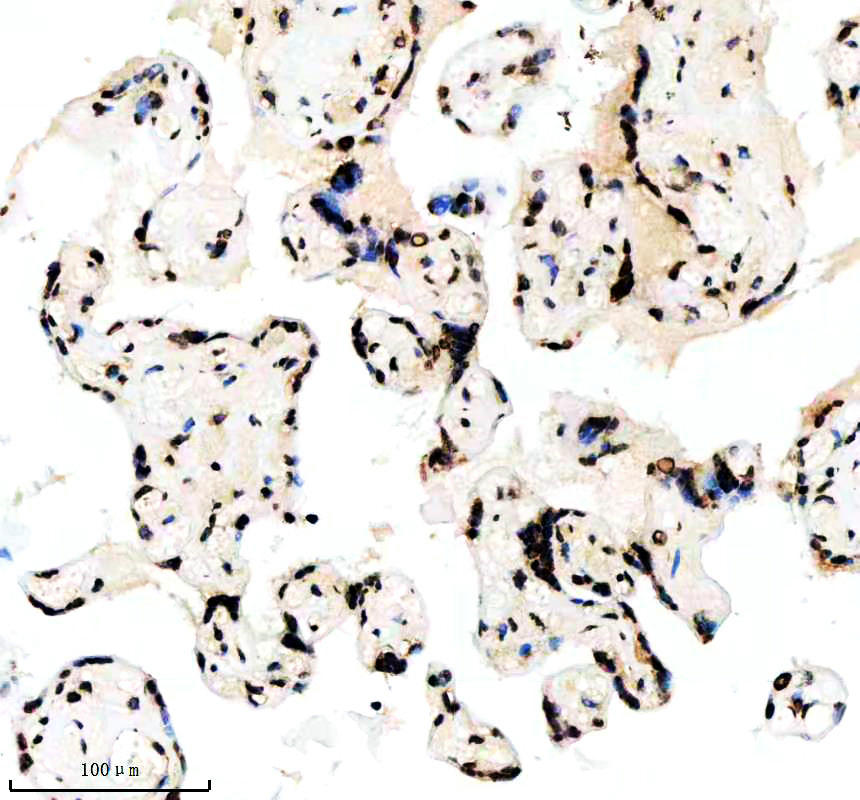

IHC analysis of Histone H3 (acetyl K14) using anti-Histone H3 (acetyl K14) antibody (BM4151) .

Histone H3 (acetyl K14) was detected in a paraffin-embedded section of human placenta tissue. The tissue section was incubated with rabbit anti-Histone H3 (acetyl K14) Antibody (BM4151) at a dilution of 1:200 and developed using HRP Conjugated Rabbit IgG Super Vision Assay Kit (Catalog # SV0002) with DAB (Catalog # AR1027) as the chromogen.